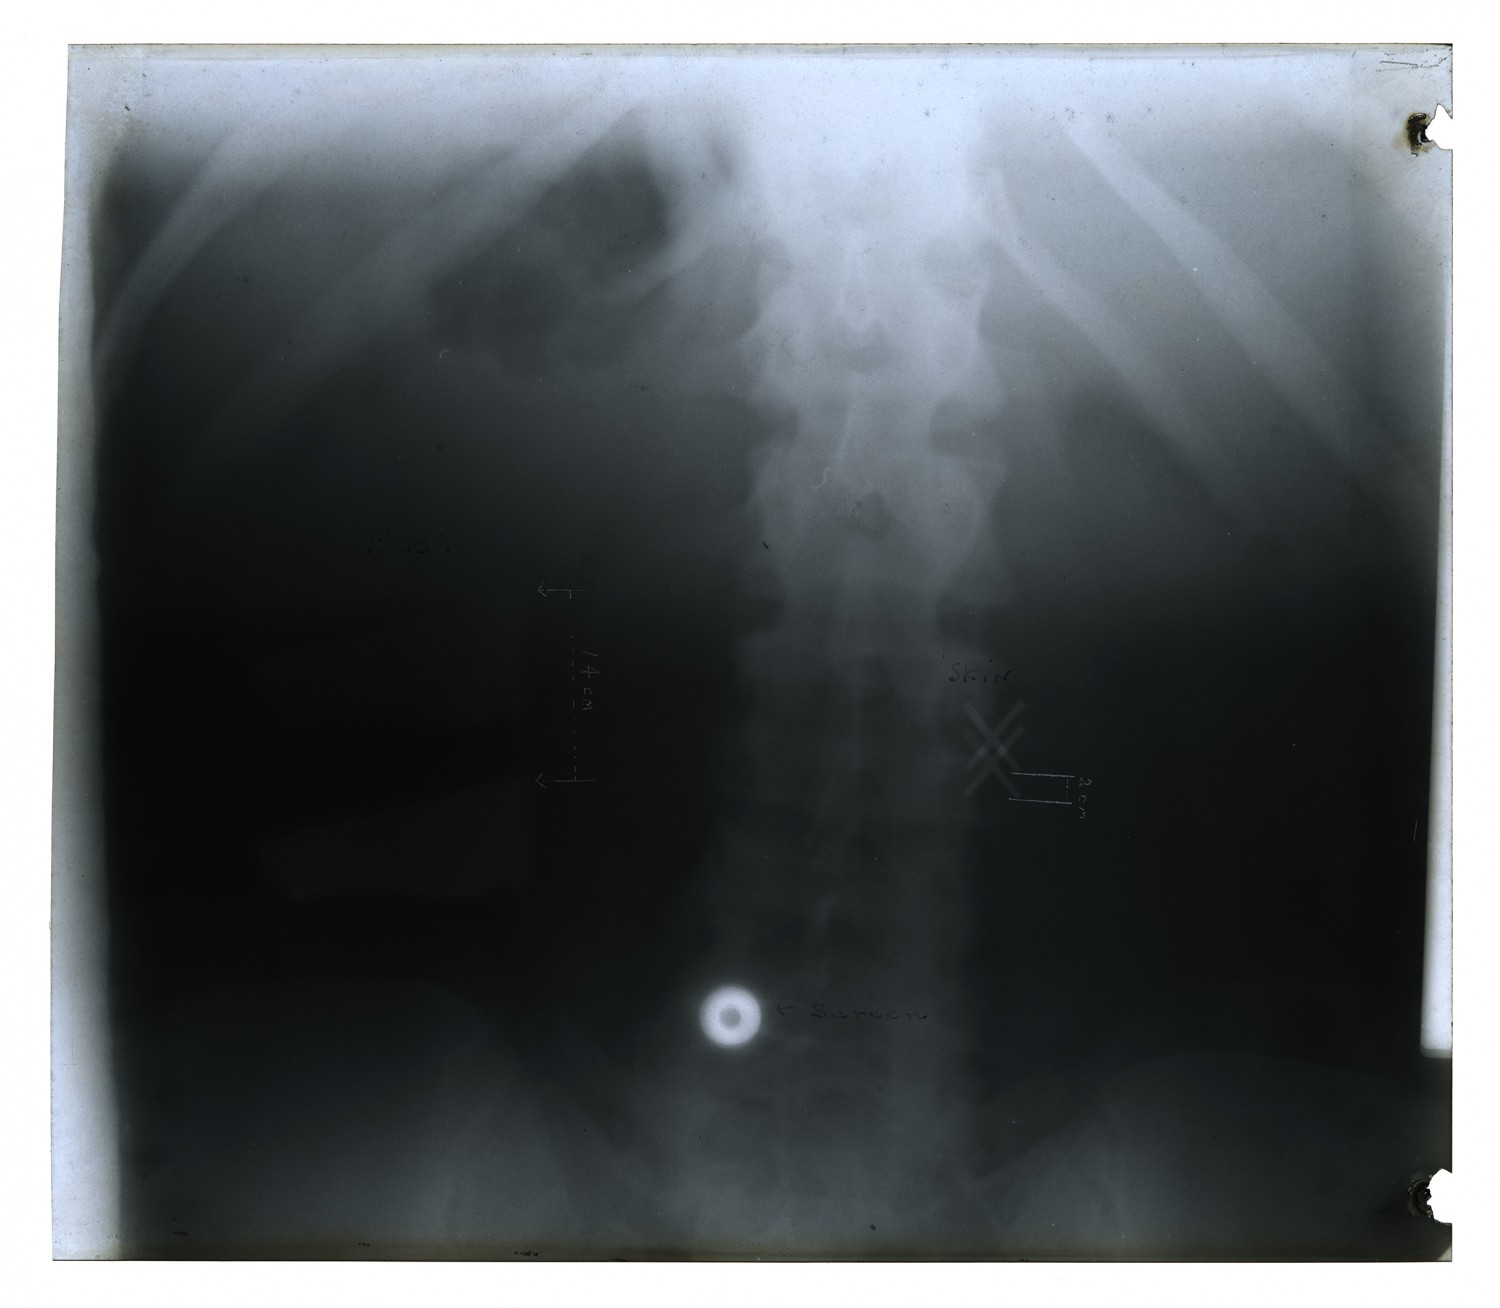

| Description | X-ray taken by Edwin C. Ernst of Base Hospital 21 in Rouen, France. Base hospital 21 was formed from faculty and students from Washington University School of Medicine. Ernst designed his own portable x-ray equipment to help quickly diagnose injured soldiers. |